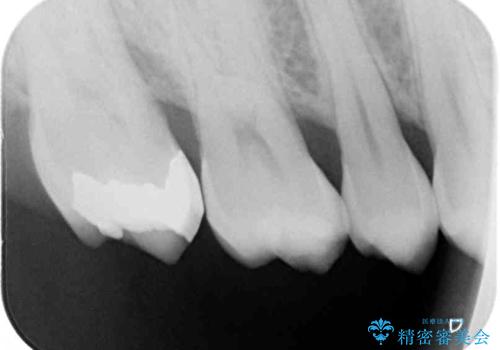

ゴールドインレーは銀歯のインレーやセラミックインレーと比べ、「技工操作の精度が高く、適合が著しく良い」というメリットがあります。特に上の奥歯は歯科医師の操作が行いにくいため、「適合の良さ」は再治療のリスクを防ぐ上でとても重要な要素となります。

上の奥歯は金属色が見えることもないため、審美的な問題は全くありません。